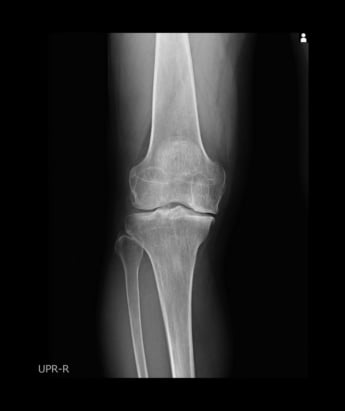

2400万人が悩む「変形性膝関節症」